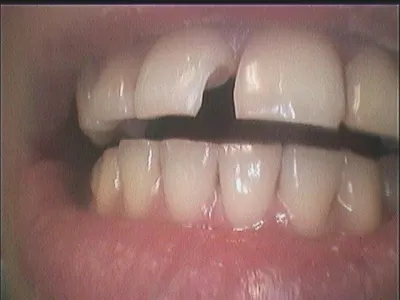

Галерея

15